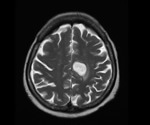

Firefighting chemicals leave brain cancer-linked mutations, study shows